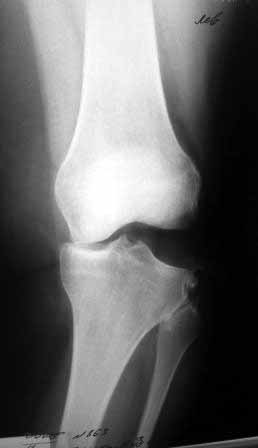

Сегодня на приеме была больная 27 лет, вес 120кг. Травма 7 лет назад - ДТП. Была ЧМТ, двухсторонний перелом пилона, обширные рваные раны бедер, голеней. Судя по нынешней картине - вывих левой голени.

Ходит практически не хромая, жалобы на неустойчивость голени при ходьбе. При стресс тестах - грубейшая несостоятельность связочного аппаратаколенного сустава. Хотелось бы услышать мнение о целесообразности пластического восстановления связок после столь длительного периоданестабильности сустава.С уважением,Leonid m

У пациентки застарелый разрыв наружной боковой связки. Нестабильность вскоре приведет к деф артрозу коленного сутсава, к тому же избыточный конституциональный вес. Делайте пластику наружной боковой связки.

Сделайте МРТ. При таком р-гене возможен разрыв задне-латерального комплекса с выраженной нестабильностью. Тактика - пластика ЗКС, ЛКС.